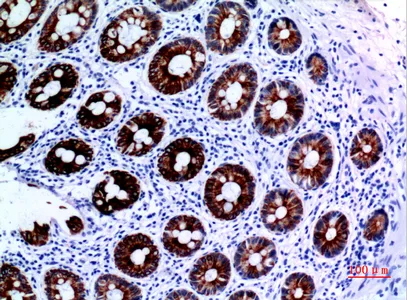

Cytokeratin 8 Rabbit Polyclonal Antibody

Cat: APRab09760

Size1:50μl Price1:$118

Size2:100μl Price2:$220

Size3:500μl Price3:$980

Size2:100μl Price2:$220

Size3:500μl Price3:$980